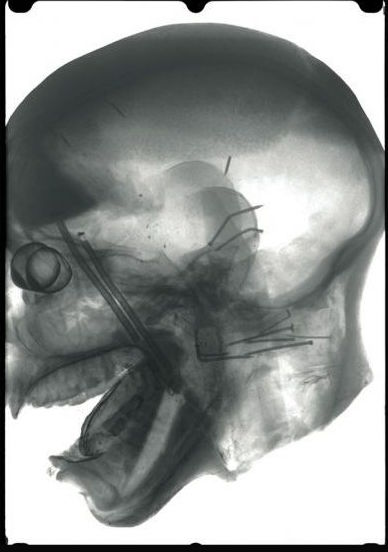

・カーネギー自然史博物館で、150年前に作られたライオンに襲われるアフリカの部族のマネキンの内部に、人間の頭蓋骨が入っていたことが判明

・マネキン頭部をCTスキャンしたところ、本物の頭蓋骨が入っていることが判明、大騒動に